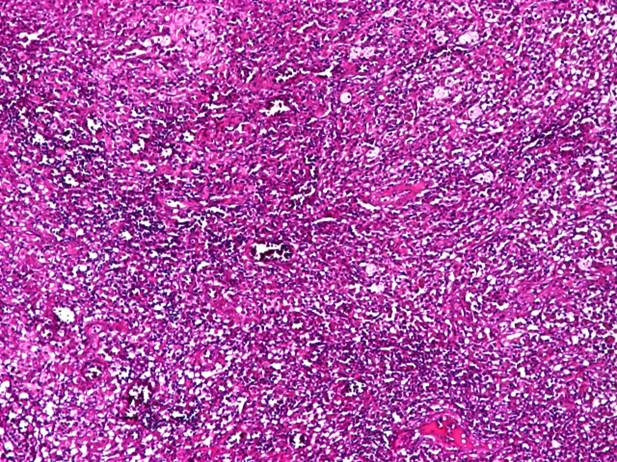

Fig 3 Hepatita cronica sever activa - fibroza si inflamatie porto-portala. HE, 10x.

Fig 4 Hepatita cronica sever

activa. HE, 4x, 10x